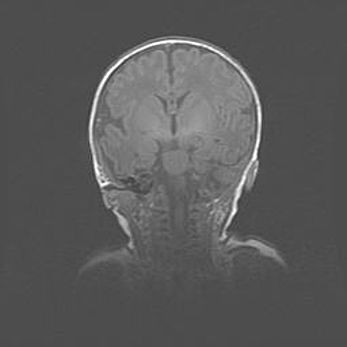

Наружная гидроцефалия с возможной атрофией височных областей.

Возраст: 28 дней

Вес: 3670 г

Пол: мужской

Окружность головы: 38 см

Срок гестации: 40 недель

Гидроцефалия головного мозга у новорожденных – это заболевание, которое характеризуется скоплением избыточного количества спинномозговой жидкости в желудочковой системе головного мозга в результате затруднения её перемещения от места выработки к месту поглощения в кровеносную систему или вследствие нарушения абсорбции. При открытой наружной форме гидроцефалии у новорожденных расширяются и переполняются субарахноидные пространства.

При нормотензивных  формах,  которые,  как  правило,  являются  следствием  перенесенных ишемических  повреждений  паренхимы  мозга,  возможно  сочетание микроцефалии  с нормотензивной гидроцефалией. В основе данных изменений лежит атрофия больших полушарий с преимущественной  локализацией  в  лобно-височных  областях.